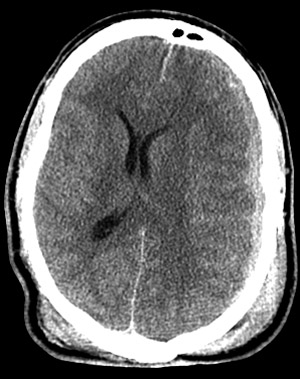

| This head CT scan in axial view above demonstrates a subdural hematoma with the classic identations juxtaposed with the gyri and sulci beneath the dura on the lateral aspect of the left cerebral hemisphere. Note the effacement of the lateral ventricles and midline shift. |